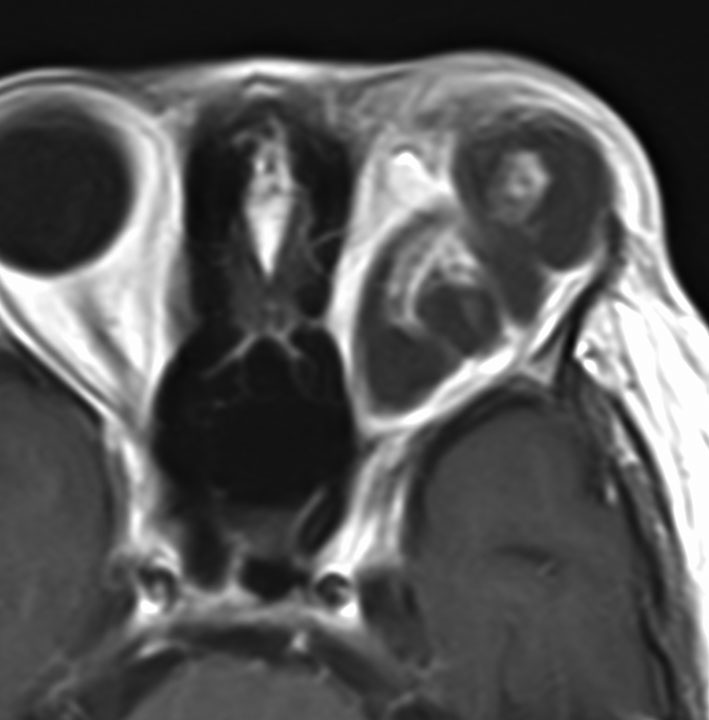

幼児の視路の毛様粘液性星細胞腫です。T2強調画像(左側)で白く高信号に写るのが特徴です。ガドリニウム増強ではまだらになっていますが,均一に真っ白に高信号になることも多いです。乳幼児のものは,ドロドロに柔らかい腫瘍です。

生後7カ月の幼児です。目が揺れるようになり(振り子様眼振)眼科を受診して腫瘍が発見されました。小児脳腫瘍の治療ができる病院へと紹介されました。

1ヶ月後にまたMRI検査がされました。乳児ですから検査にも麻酔が必要です。腫瘍は明らかに大きくなっています。左視神経から視索の腫瘍化が著しいので右側だけかすかに視力が残っているかもしれません。視力は明かりがわかる程度(明暗弁)と評価されました。